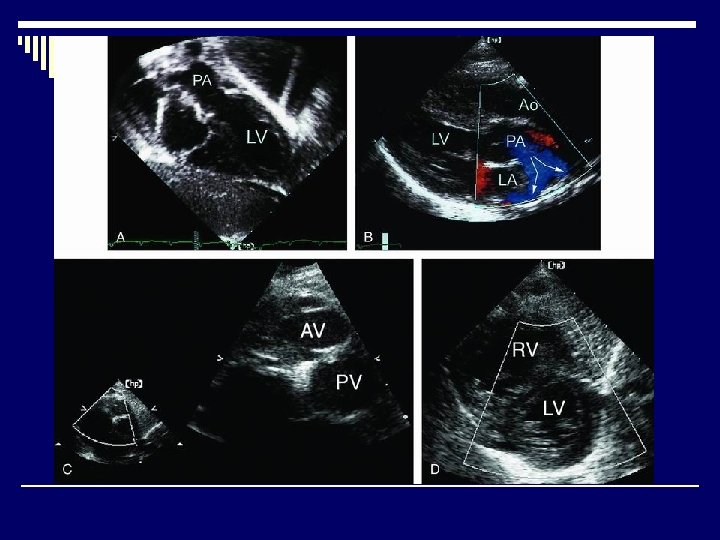

Echocardiography o. Diagnosis o. Decision-making o. Pre-and post-operative evaluation

TOF